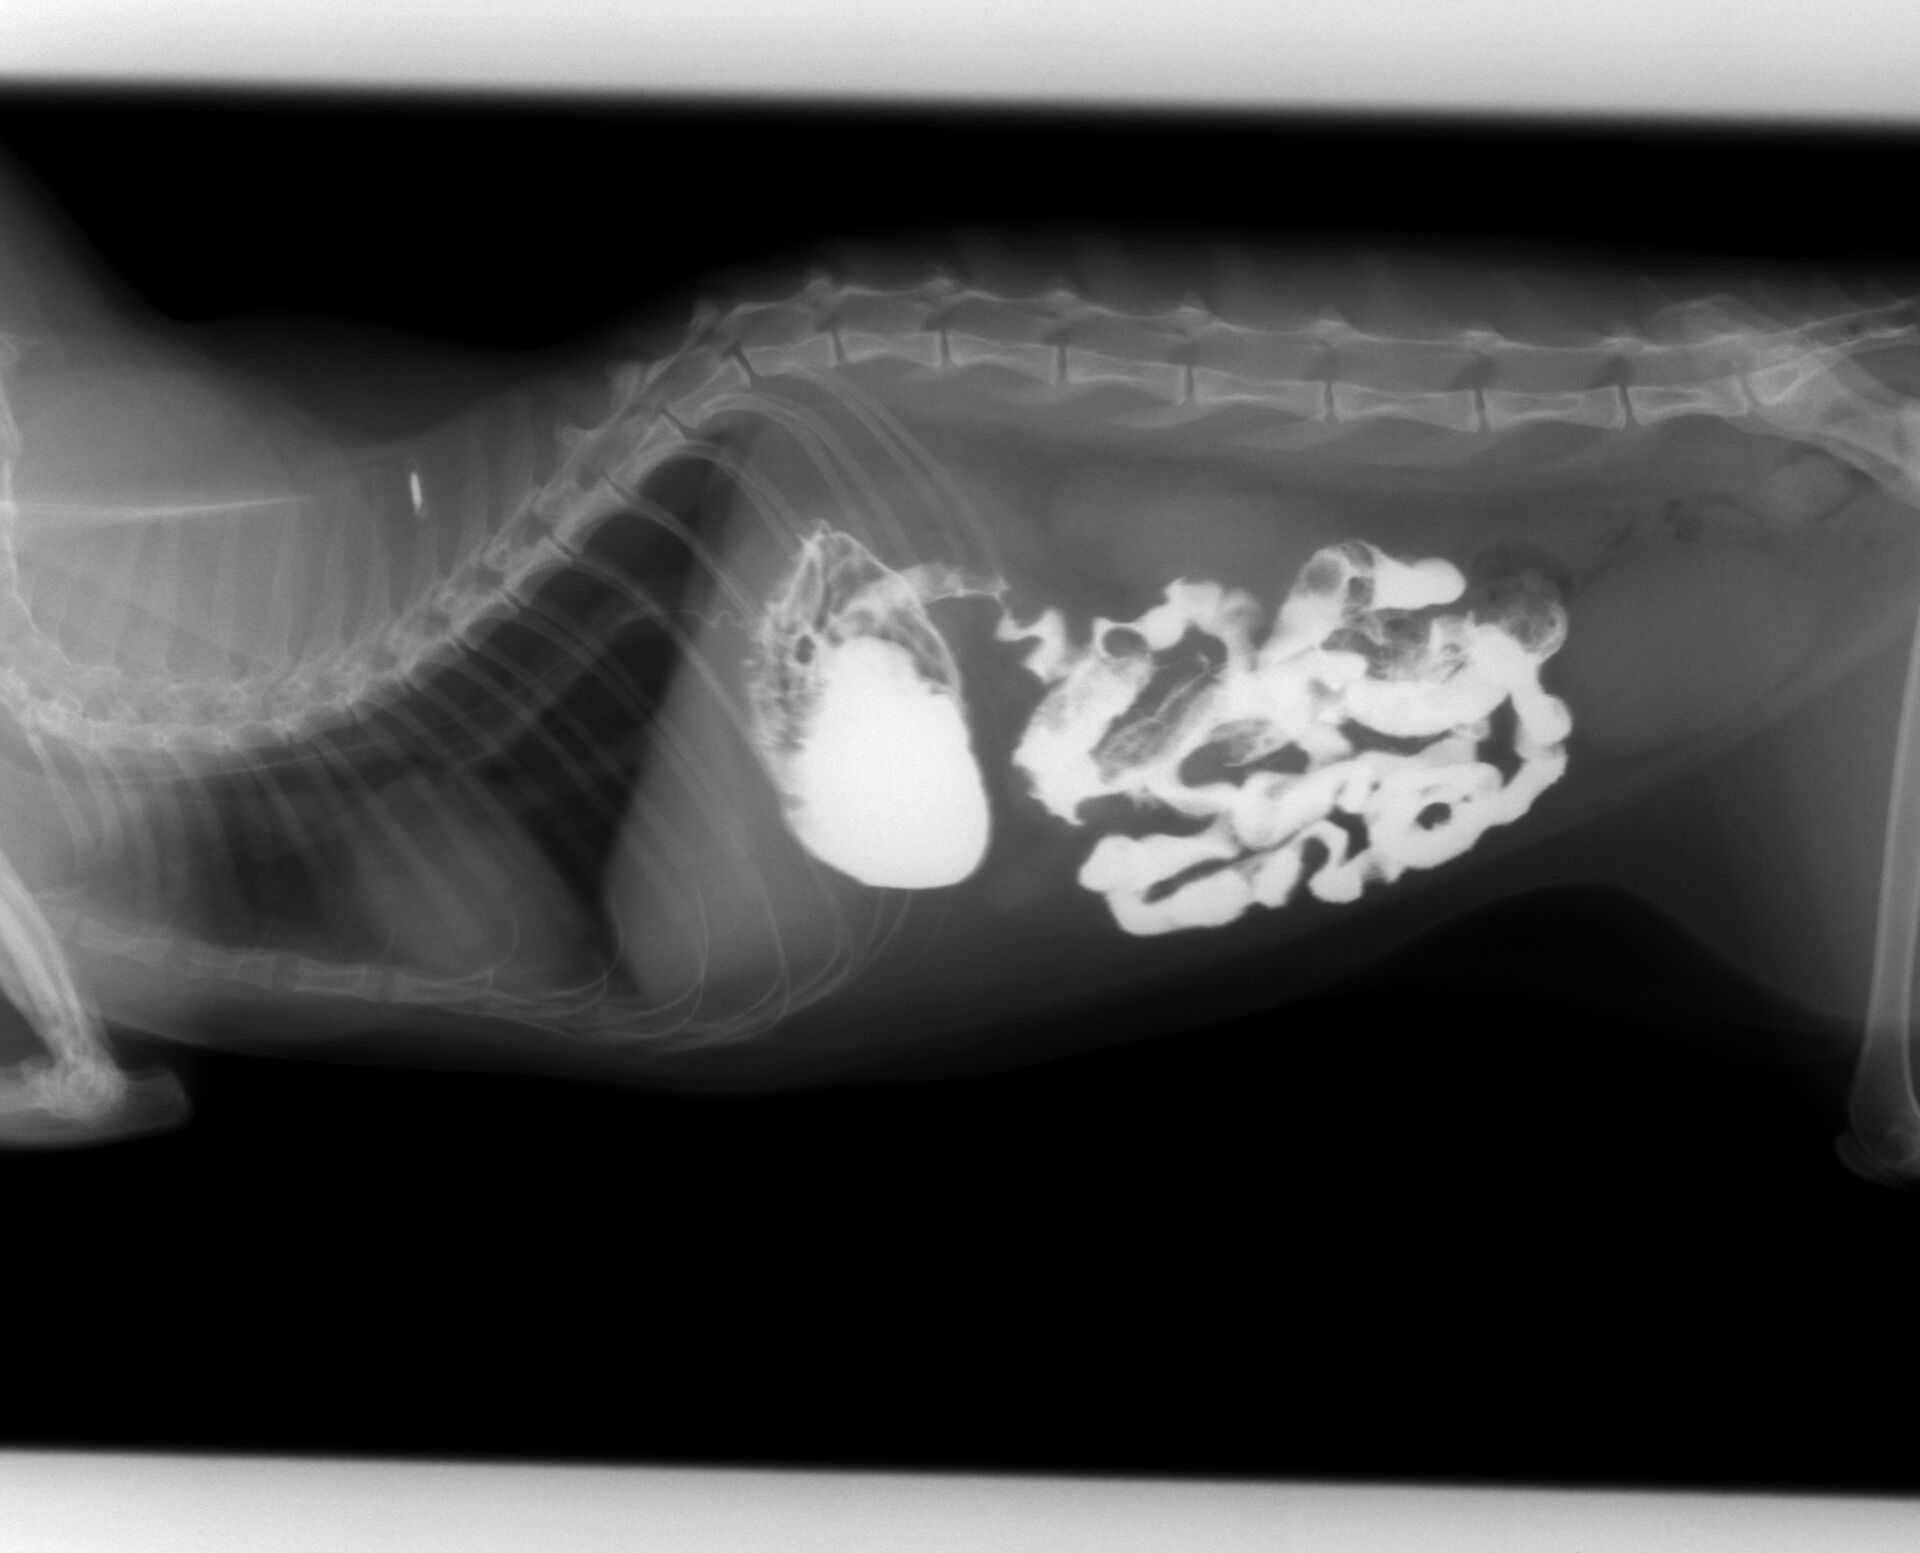

猫の紐状異物の誤嚥についてです。突然、ある日を境に食欲がなくなり、水を飲むたびに嘔吐してしまう、ということで来院されました。お腹を触った時に少し痛がるような仕草をしたので、誤嚥を疑いましたが、飼い主さんは「考えにくい。」ということでした。ですが、口腔内を観察してみますと、奥歯に紐のようなものが絡んでいるのが認められました。紐状異物の誤嚥の可能性が考えられましたので、バリウム検査をしました。その結果が下の写真です。

バリウムを飲ませた直後の写真ですが、矢印で示していますように食道にバリウムが残っています。これは紐状異物が食道にあることを示しています。その後4時間まで撮影しました。その結果が下の写真です。小腸まで達したバリウムは小腸の変形を示しています。これは紐状異物が小腸まで達していることを示しています。